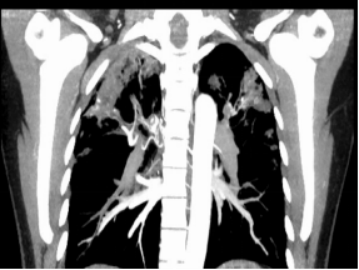

3、右肺上叶支气管动脉增迂曲;主动脉钙化。

入院经积极药物止血治疗后患者仍反复咯血,考虑支气管动脉畸形所致出血,于2021-12-28在局麻下行支气管动脉造影、栓塞术,术后未再咯血,效果良好。